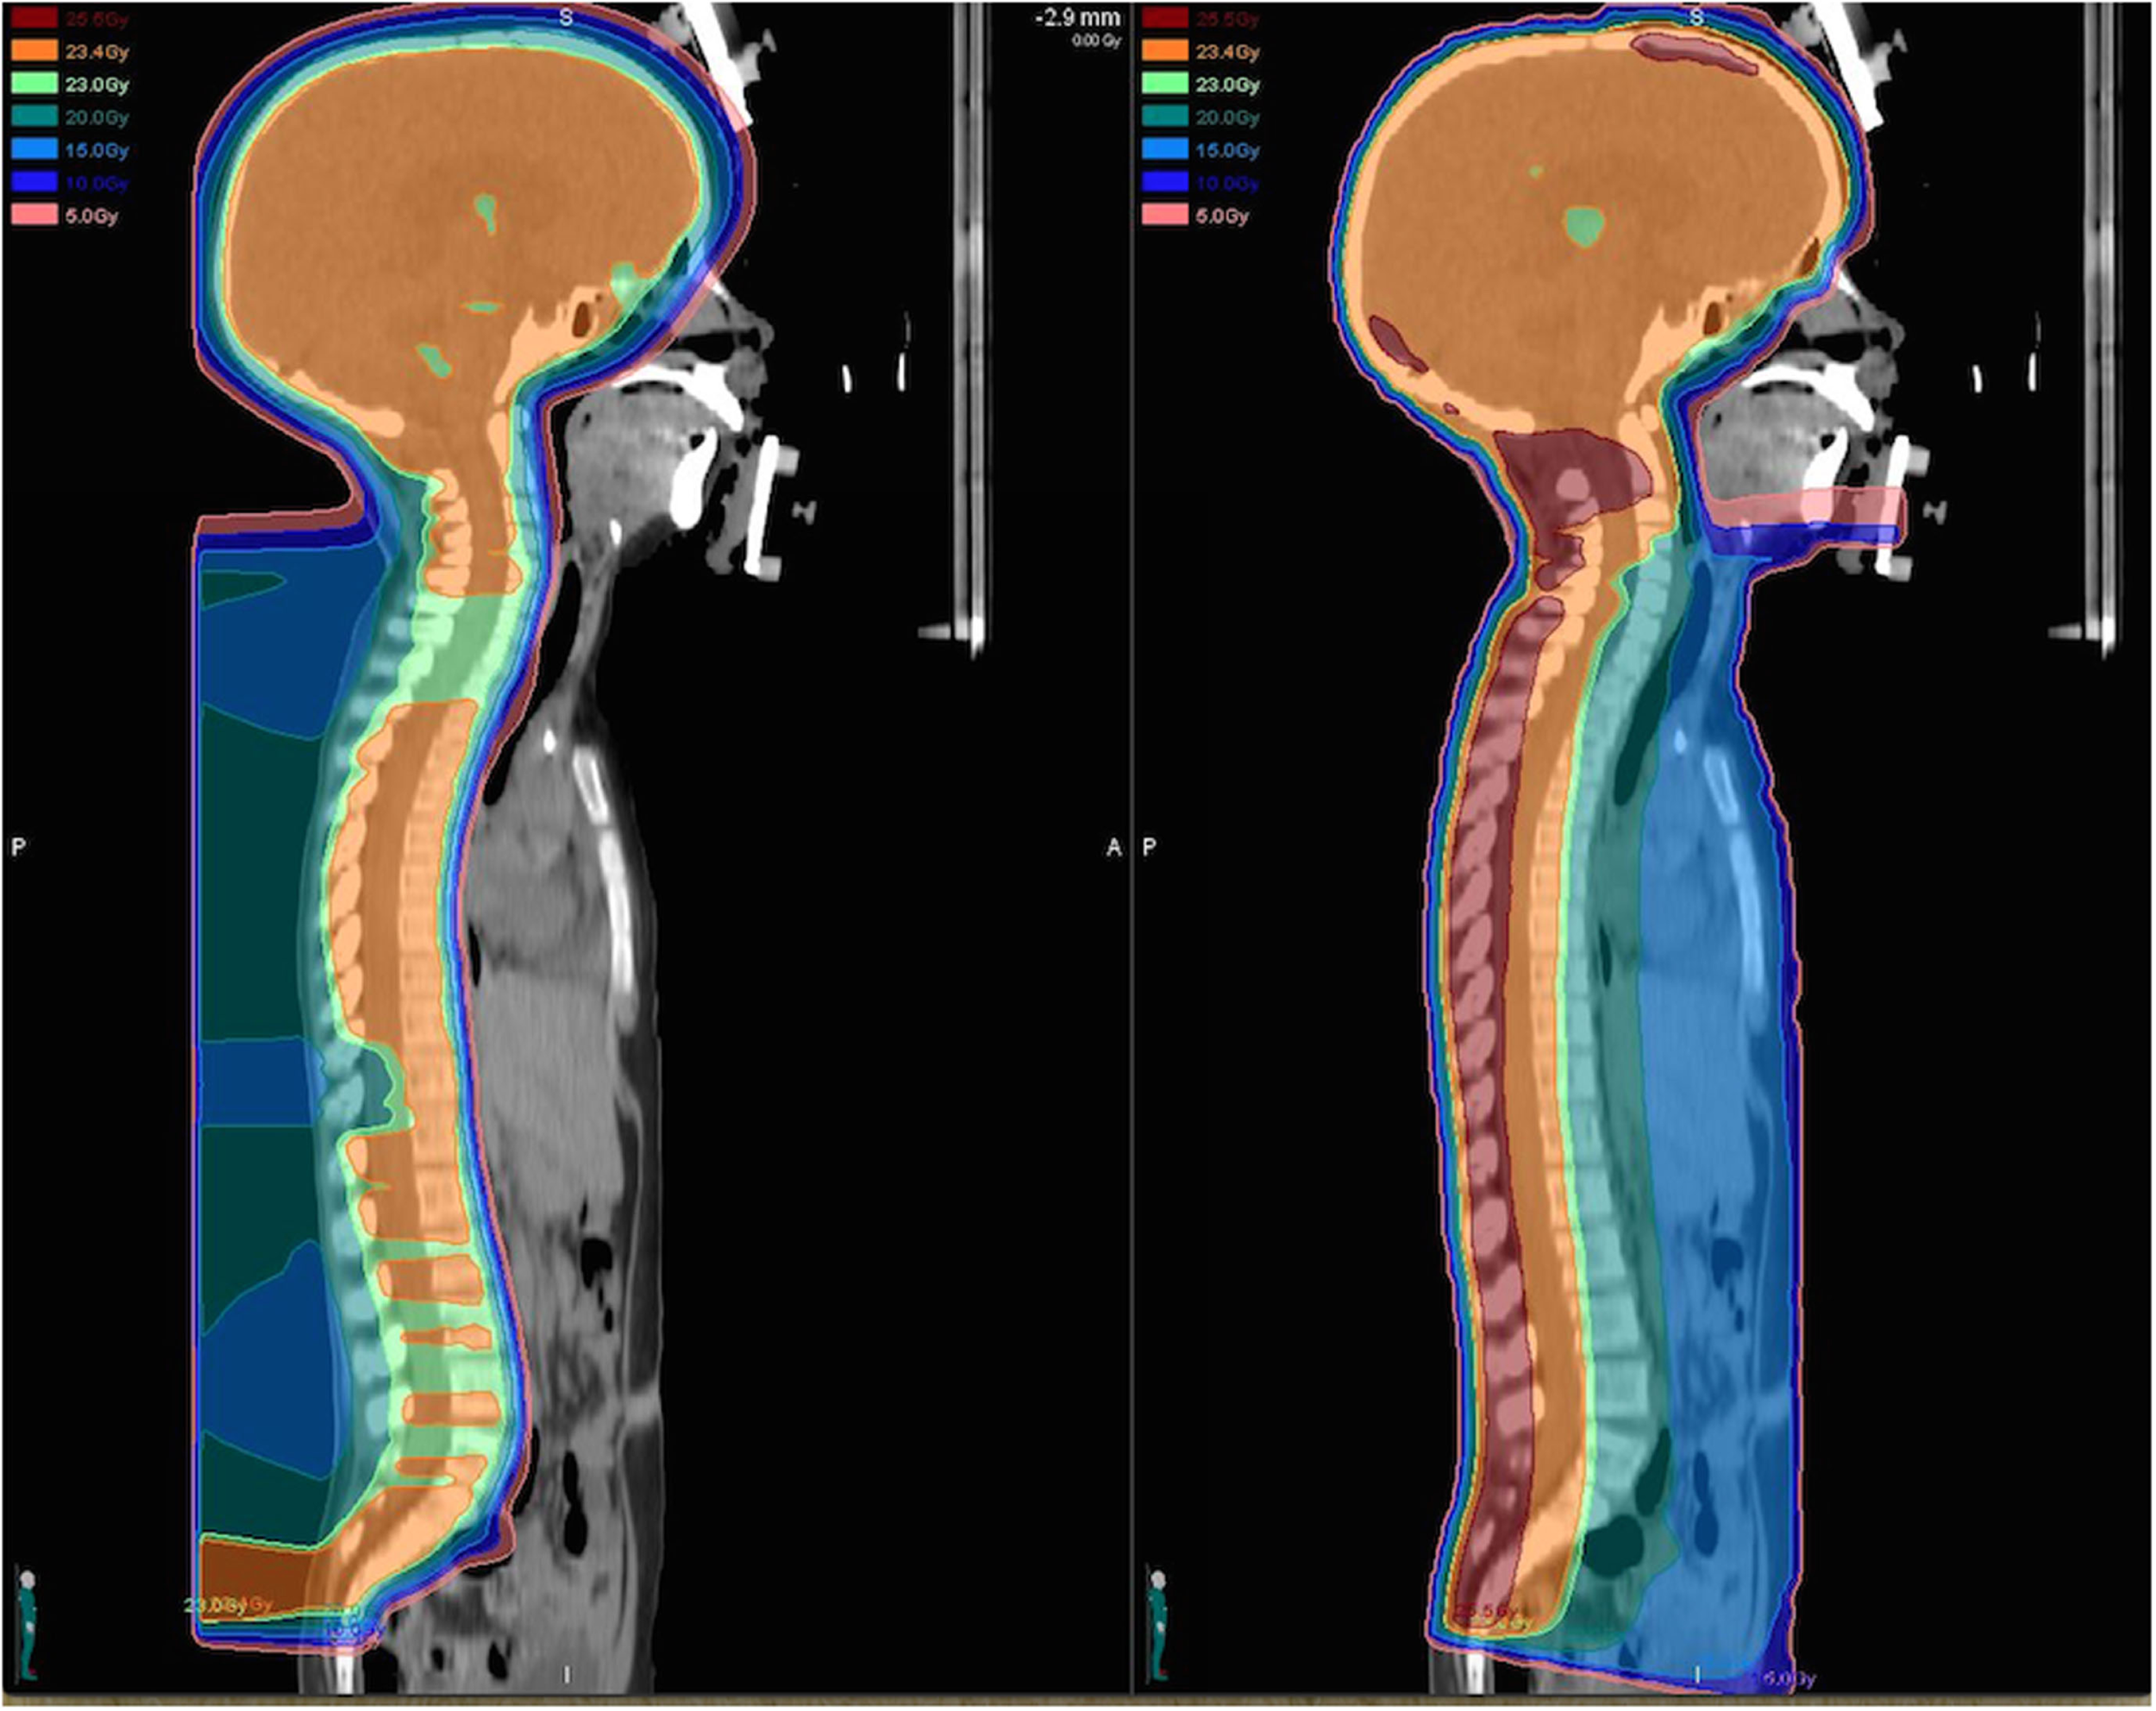

In a treatment planning comparison study evaluating PRT in comparison to standard photon techniques and intensity-modulated radiation therapy (IMRT) for a variety of malignancies, the use of protons has been demonstrated to substantially reduce the volume of normal tissues receiving medium to low doses (below about 70% of the target dose) when compared with both standard and IMRT photon plans (8). Over all cases, the use of protons lead to a reduction of the total integral dose by a factor of three compared to standard photon techniques and at least a factor of two compared to intensity-modulated photon plans (8). Many similar dosimetric comparison studies have been performed for a variety of specific tumor types among children and adults and have clearly demonstrated the superior ability of PRT to spare normal tissues from unwanted radiation (9–12). With the use of craniospinal irradiation for medulloblastoma, the dosimetric benefit of protons is particularly striking as organs anterior to the vertebrae are spared from receiving unwanted radiation with PRT (12) (Figure 1). In effort to quantify the effect of the reduced total integral dose delivered with PRT on secondary malignancy risk, studies have further utilized modeling systems based on dosimetric comparisons, organ equivalent dose, and radiation protection models to approximate the benefit of protons with regard to second malignancies.

Figure 1

Dose distributions for a proton (left) and photon (right) craniospinal plan prescribed to 23.4 Gy (relative biological equivalents) are illustrated for comparison. The proton craniospinal plan provides considerable sparing of normal tissues anterior to the spinal canal and delivers a significantly reduced total integral dose to the patient.